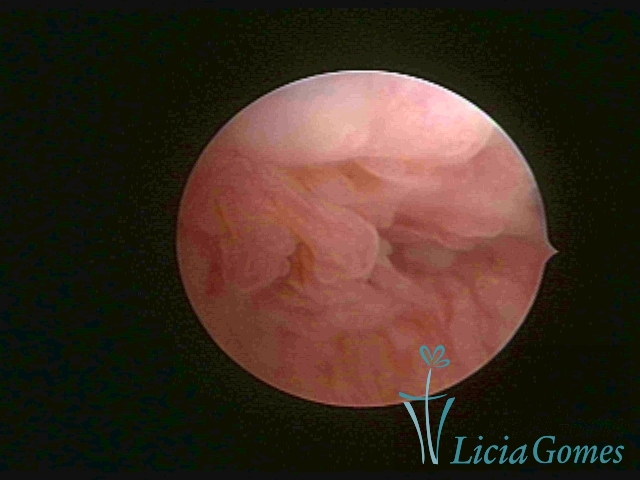

• First part or proximal section or lower section, presence of a light, crystalline mucus, presence of crypts, microvesicular (resembling grape clusters.)